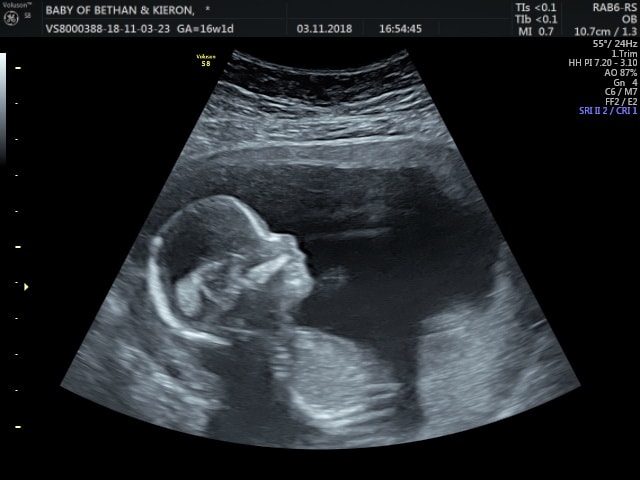

मंडळी, युकेची बेथन सिम्पसन या महिलेच्या पोटातून साडेचार महिन्याचं बाळ शस्त्रक्रियेने बाहेर काढण्यात आलं होतं. या बाळावर एक खास पद्धतीची शस्त्रक्रिया केल्यानंतर बाळाला पुन्हा गर्भात ठेवण्यात आलं.

अत्यंत कठोर अशा निकषांवर ही शस्त्रक्रिया करण्यात आली आहे. शस्त्रक्रियेच्या अगोदर बेथनला चाचण्या आणि स्कॅन्स मधून जावं लागलं. या सगळ्यातून गेल्यानंतर शस्त्रक्रियेसाठी मंजुरी मिळाली. युके मध्ये या प्रकारच्या शस्त्रक्रियेची ही चौथी वेळ आहे.

ही शस्त्रक्रिया आई आणि बाळासाठी धोकादायक होती. पण सुदैवाने शस्त्रक्रिया यशस्वी झाली आहे.

अशा प्रकारच्या शस्त्रक्रियेला त्याच प्रकारचं मोठं कारणही लागतं. या केस मध्ये बेथनच्या बाळाच्या शरीरात ‘स्पिना बिफिडा’ नावाचा दोष होता. पाठीच्या कण्याची पूर्ण वाढ न झाल्याने हा दोष उद्भवतो. खालील फोटो मध्ये याचं उदाहरण तुम्ही पाहू शकता.